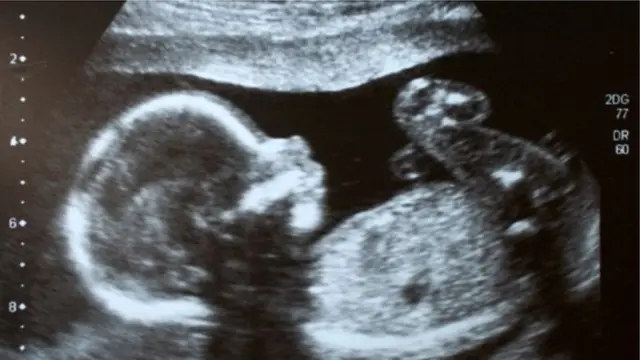

চীনে মায়ের গর্ভস্থ শিশুর জিন পাল্টে দেয়ার সন্দেহজনক দাবি ডাক্তারের

জিনগত পরিবর্তনের মাধ্যমে পৃথিবী এই প্রথম একটি মানব-সন্তান পেয়েছে বলে দাবি করেছেন এক চীনা বিজ্ঞানী।

মায়ের পেটে ভ্রূণ অবস্থায় রেখেই জেনেটিকেলি বা জিনগত কিছু পরিবর্তন ঘটিয়েছেন বলে দাবি করেছেন অধ্যাপক হি জনকুই।